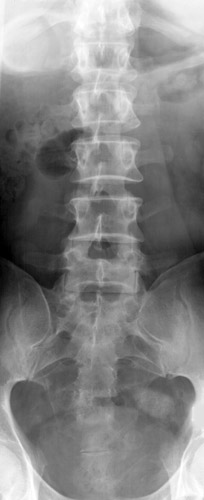

Look for the compression fractures in the radiographs below. Can you find them?

Click on the image for the answer.

AP view